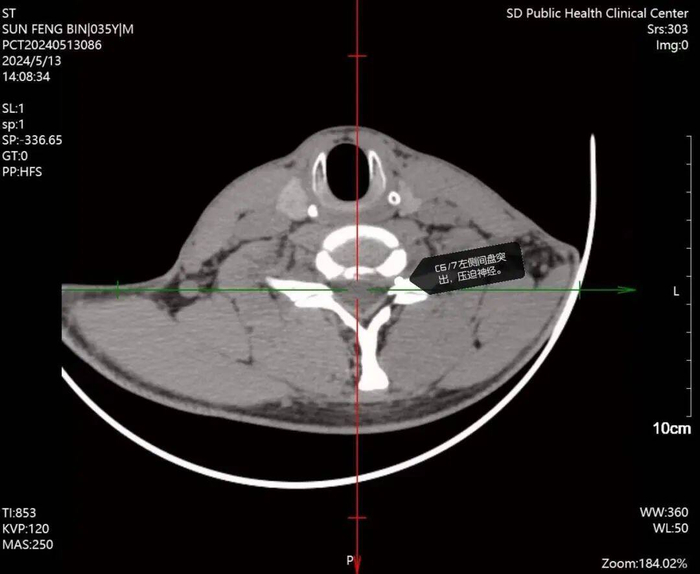

高主任通过详细查体及影像学检查(CT/MRI)发现,患者颈椎C5/6节段椎间盘突出,左侧神经根严重受压,确诊为“神经根型颈椎病”。

精准微创手术:两处0.5cm切口破解难题

针对患者保守治疗无效、疼痛剧烈的特点,高红伟主任团队采用国际前沿的UBE-Keyhole脊柱内镜技术,实施微创手术:

1.手术原理:经颈部后方两处0.5厘米微小切口,利用双通道内镜系统精准定位,切除突出椎间盘、扩大椎管容积,彻底解除神经根压迫。